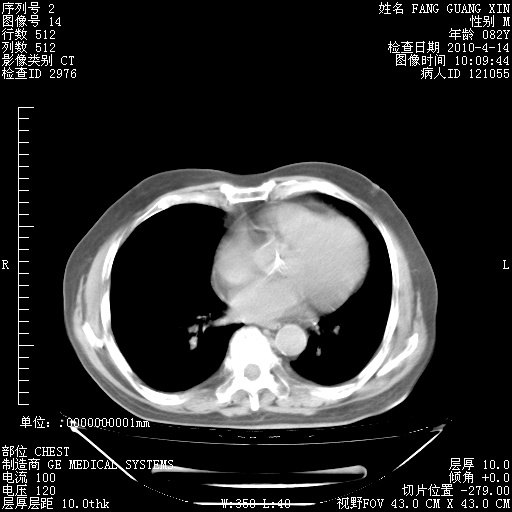

4月14日肺部CT